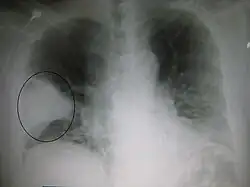

Billeder

Et røntgenbillede af thorax (brystkassen) bruges ofte til diagnoser.[10] Patienter med milde tilfælde skal kun røntgenfotograferes, hvis der er mulighed for komplikationer, eller patienten ikke har reageret på behandlingen, eller hvis årsagen er ukendt.[10][38] Hvis patienten er så syg, at man må indlægge, anbefales det at tage røntgenbilleder.[38] Billedet viser ikke altid sygdommens sværhedsgrad og kan ikke skelne mellem bakterie- og virusinfektion.[10]

Røntgenbilleder af lungebetændelse kan vise lobær pneumoni, bronkopneumoni (også kendt som betændelse i en lungeklap eller pletvis udbredt lungebetændelse) og interstitiel pneumoni.[41] Bakteriel lungebetændelse erhvervet uden for sygehus viser sig typisk ved lungekonsolidering af et lungesegment, og det kaldes lobær eller primær pneumoni.[20] Men andre mønstre kan vise sig ved andre typer lungebetændelse. Ved aspirationspneumoni kan der være uklare områder nederst i begge lunger og i højre side.[20][20] Hvis lungebetændelsen er viral, kan røntgenbilleder se normale ud, eller de kan vise hyperinflation, pletter i begge sider eller de kan ligne billeder af bakterielle lungebetændelser med lungekonsolidering.[20] Røntgenbilleder viser måske ikke noget tidligt i forløbet, især, hvis patienten er dehydreret, eller de kan være svære at tyde, hvis patienten er overvægtig eller tidligere har haft lungesygdomme.[11] En CT-skanning kan give yderligere oplysninger, hvis det kræves.[20]